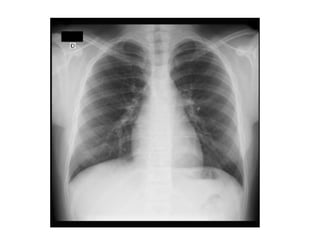

INCIDÊNCIAS DO TÓRAX

•1. Póstero-anterior: evitar a magnificação do coração e

possibilita o posicionamento dos ombros de tal forma que a

escápula fique fora do filme.

•2. Ântero-posterior: crianças pequenas e pacientes

acamados devido a dificuldade de posicionamento.

•3. Perfil: Usa-se perfil esquerdo para evitar magnificação do

coração. Sempre solicitada com a PA.

IDENTIFICAÇÃO DA RADIOGRAFIA

PA

Usa-se incidência PA

devido a localização

anatômica do coração.

Quanto mais perto do filme

menor a magnificação e

maior nitidez.